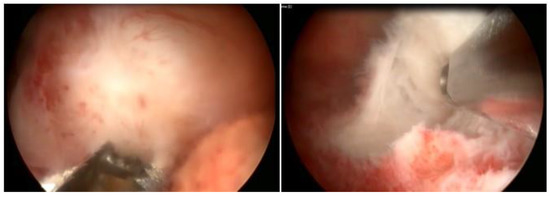

3.4. Slicing Technique

The principle of the slicing or slicing technique is the partial and progressive removal of the myoma, in fragments, starting at its surface and gradually working towards its base. Slices of myoma are removed with the semicircle loop in the mono or bipolar resectoscope, moving it energized, from the fundus to the cervix. The distension medium is different according to the type of energy; with monopolar energy, non-electrolytic media are used, which are 1.5% glycine, mannitol, and mannitol/sorbitol, while, with bipolar energy, the electrolytic media, physiological solute 0.9%, and ringer lactate are used [27] (Figure 10).

3.5. Morcellator Technique (Hysteroscopic Mechanical Tissue Removal)

Hysteroscopic Tissue Removal Systems (TRS) perform fragmentation and suction of endometrial pathology, such as polyps and fibroids. There are three main brands currently available on the market (e.g., Myosure, Truclear, and Symphion) and they are mainly used for types 0 and 1 intrauterine leiomyomas. A rapidly rotating blade resects small portions of the fibroid, and these are suctioned into a tissue trap for pathologic evaluation. This technique alleviates the need for removal of fibroid “chips” from the cavity and it has been shown to be faster for trainees.

Hysteroscopic tissue removal systems introduced an efficient, easy-to-use tool for hysteroscopic myomectomy. However, there are limitations, such as the high cost of the disposable element, as well as the difficulty resecting fundal fibroids and deep type 2 fibroids. In addition, dense and calcified fibroids can be very challenging to resect with these devices. One study showed that switching to a resectoscope in these cases allowed for finalization of the procedure [28]. However, another meta-analysis showed statistically significant improvement in complete resection of pathology when tissue extraction devices were used [29]. The surgeon should tactfully choose the best tool based on the pathology, its size, location, the patient’s goals, and the surgeon’s expertise.

The technique of surgery at the hospital is the same as that of the outpatient clinic, also with the physiological solute as distension media, with hospital surgery being more indicated for submucosal myoma. Due to the difficulty in fragmenting fibroids with smaller-caliber blades, surgery in the operating room, with instruments of greater caliber and power, makes myomectomy feasible with less operative time and improved efficiency [30,31].

Morcellators have expanded their use, with good acceptance, especially by those who are starting hysteroscopic surgery, due to practicality of use, short learning time, and non-use of energy (only mechanics), with good performance in the treatment of intracavitary lesions. Its limits are more intramural lesions, and lesions in cornual and fundic regions (Figure 11).

Figure 10. Slicing technique.

Figure 11. Morcellator technique—hysteroscopic mechanical tissue removal.